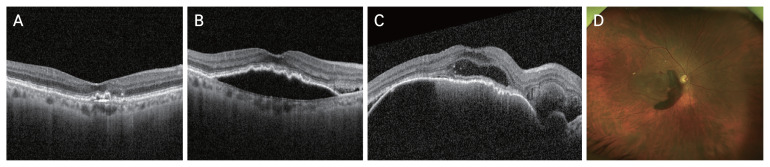

{"title":"Predictive Factors for Submacular Hemorrhage in Age-related Macular Degeneration: A Retrospective Study.","authors":"Hanwool Moon, Hyun Goo Kang, Junwon Lee, Christopher Seungkyu Lee, Min Kim, Suk Ho Byeon, Sung Soo Kim","doi":"10.3341/kjo.2024.0032","DOIUrl":null,"url":null,"abstract":"<p><strong>Purpose: </strong>Little is known about the major risk factors for submacular hemorrhage (SMH). This study aimed to evaluate the factors associated with SMH in patients with neovascular age-related macular degeneration (nAMD) and polypoidal choroidal vasculopathy receiving three consecutive loading doses of intravitreal aflibercept or ranibizumab injections.</p><p><strong>Methods: </strong>This retrospective cross-sectional study included 48 patients diagnosed with nAMD and polypoidal choroidal vasculopathy who completed three loading doses under a treat-and-extend regimen. Patients were divided into the SMH group and the non-SMH group (age- and sex-matched without SMH), with 24 patients in each group. Intravitreal injections, agents, and optical coherence tomography (OCT) features were compared.</p><p><strong>Results: </strong>In the SMH group, SMH occurred approximately 3.29 years after post-nAMD diagnosis. The non-SMH group received more intravitreal injections of aflibercept and brolucizumab during the follow-up period after the initial loading phase. The SMH group exhibited a higher prevalence of serous/hemorrhagic pigment epithelial detachments (PEDs) at the last visit before SMH occurrence compared to the non-SMH group. Patients with a PED increase in the past two visits showed a higher tendency in the SMH group. No other OCT features significantly correlated with SMH development.</p><p><strong>Conclusions: </strong>The presence of serous/hemorrhagic PEDs may indicate a higher risk of SMH, and eyes with these features should be closely monitored to prevent sudden and devastating visual loss caused by SMH.</p>","PeriodicalId":101356,"journal":{"name":"Korean journal of ophthalmology : KJO","volume":" ","pages":"471-479"},"PeriodicalIF":0.0000,"publicationDate":"2024-12-01","publicationTypes":"Journal Article","fieldsOfStudy":null,"isOpenAccess":false,"openAccessPdf":"https://www.ncbi.nlm.nih.gov/pmc/articles/PMC11647097/pdf/","citationCount":"0","resultStr":null,"platform":"Semanticscholar","paperid":null,"PeriodicalName":"Korean journal of ophthalmology : KJO","FirstCategoryId":"1085","ListUrlMain":"https://doi.org/10.3341/kjo.2024.0032","RegionNum":0,"RegionCategory":null,"ArticlePicture":[],"TitleCN":null,"AbstractTextCN":null,"PMCID":null,"EPubDate":"2024/10/22 0:00:00","PubModel":"Epub","JCR":"","JCRName":"","Score":null,"Total":0}

Purpose: Little is known about the major risk factors for submacular hemorrhage (SMH). This study aimed to evaluate the factors associated with SMH in patients with neovascular age-related macular degeneration (nAMD) and polypoidal choroidal vasculopathy receiving three consecutive loading doses of intravitreal aflibercept or ranibizumab injections.

Methods: This retrospective cross-sectional study included 48 patients diagnosed with nAMD and polypoidal choroidal vasculopathy who completed three loading doses under a treat-and-extend regimen. Patients were divided into the SMH group and the non-SMH group (age- and sex-matched without SMH), with 24 patients in each group. Intravitreal injections, agents, and optical coherence tomography (OCT) features were compared.

Results: In the SMH group, SMH occurred approximately 3.29 years after post-nAMD diagnosis. The non-SMH group received more intravitreal injections of aflibercept and brolucizumab during the follow-up period after the initial loading phase. The SMH group exhibited a higher prevalence of serous/hemorrhagic pigment epithelial detachments (PEDs) at the last visit before SMH occurrence compared to the non-SMH group. Patients with a PED increase in the past two visits showed a higher tendency in the SMH group. No other OCT features significantly correlated with SMH development.

Conclusions: The presence of serous/hemorrhagic PEDs may indicate a higher risk of SMH, and eyes with these features should be closely monitored to prevent sudden and devastating visual loss caused by SMH.